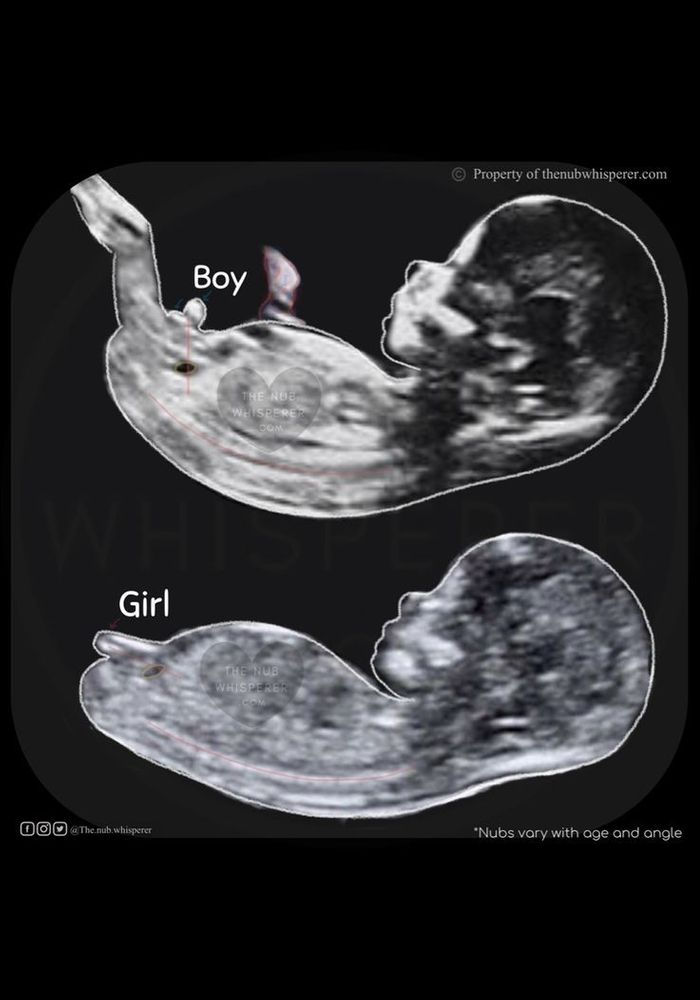

Пол ребёнка по узи, кто что видит?

Здравствуйте, видела тут девчонки на форуме, специалисты и видят по узи, нам уже 12 недель и 3 дня

Девочка

Вижу девочку, но это не точно. Сейчас пока только предположить можно.